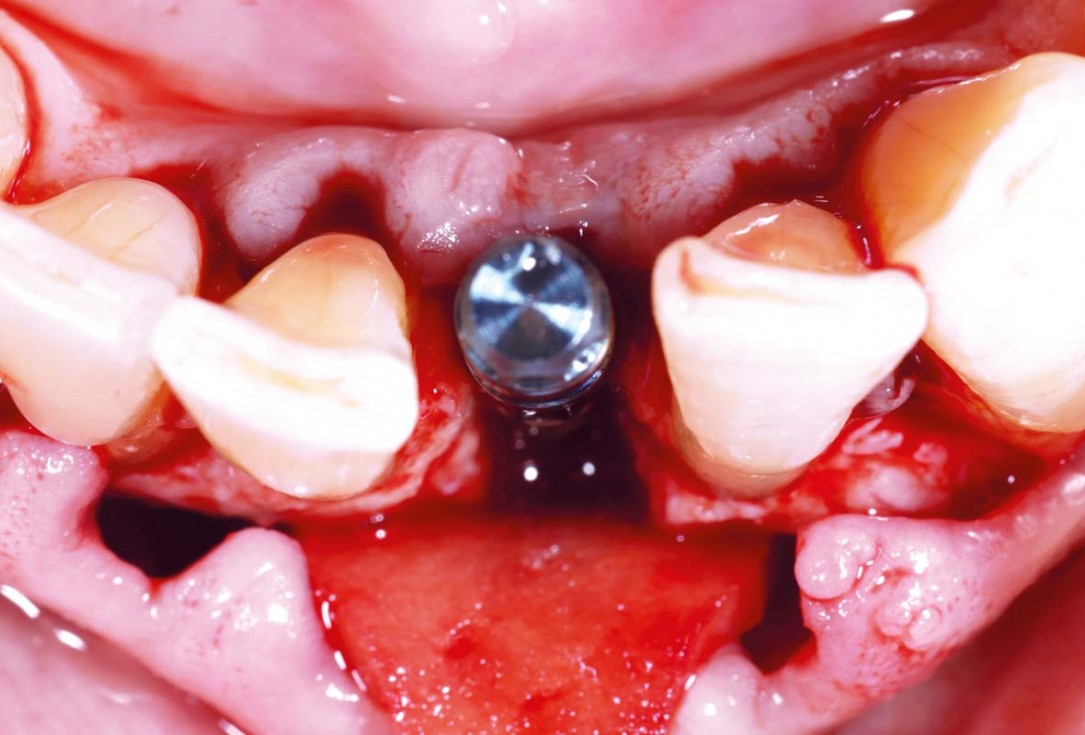

Immediate implant placement in the maxilla with contour GBR - Dr. K. Loukas

Immediate implant placement using cerabone® and collagen fleece - Dr. D. Jelušić